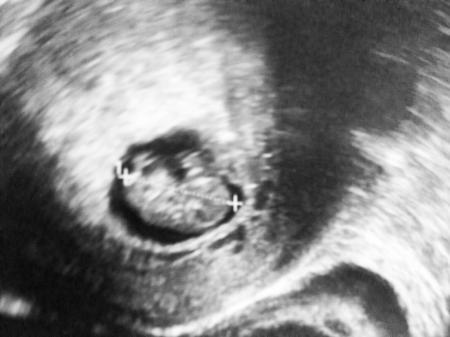

....wird kleiner. Ich freu mich total und Krümel geht es super, hat sogar an der Hand genuckelt. SSL jetzt 2,16 cm und wenn's so weiter geht kann ich in 2-3 Tagen nach Hause. Danke für eure Daumen. Ich drück euch.

Tolle Nachrichten und superschönes Foto, freut mich sehr!